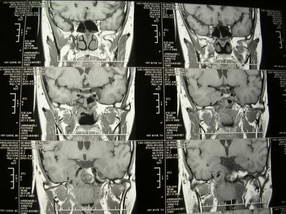

男、30、发现鼻咽部肿瘤侵犯海绵窦,未发现明显淋巴肿。请问国内那家医院治疗鼻咽部肿瘤最好?手术以何种方式为主?病灶可否全部切除?急切期待的大家的帮助。

扫描示鼻咽腔不对称,中度狭窄,右侧咽隐窝消失,局部软组织肿块,鼻咽右侧壁增厚形成肿块,突入鼻咽腔,肿块平扫呈等密度,肿块向深部侵润,右侧翼内外肌受侵,右侧咽旁间隙变窄;向后生长,头长肌界线欠清,向后上生长侵犯同侧颈动脉鞘区。双侧海绵窦增宽,内见软组织影与鼻咽部肿块相连。考虑鼻咽癌。鼻咽癌主要是放射治疗,且效果较好;到当地有治疗设备较大医院治疗即可。